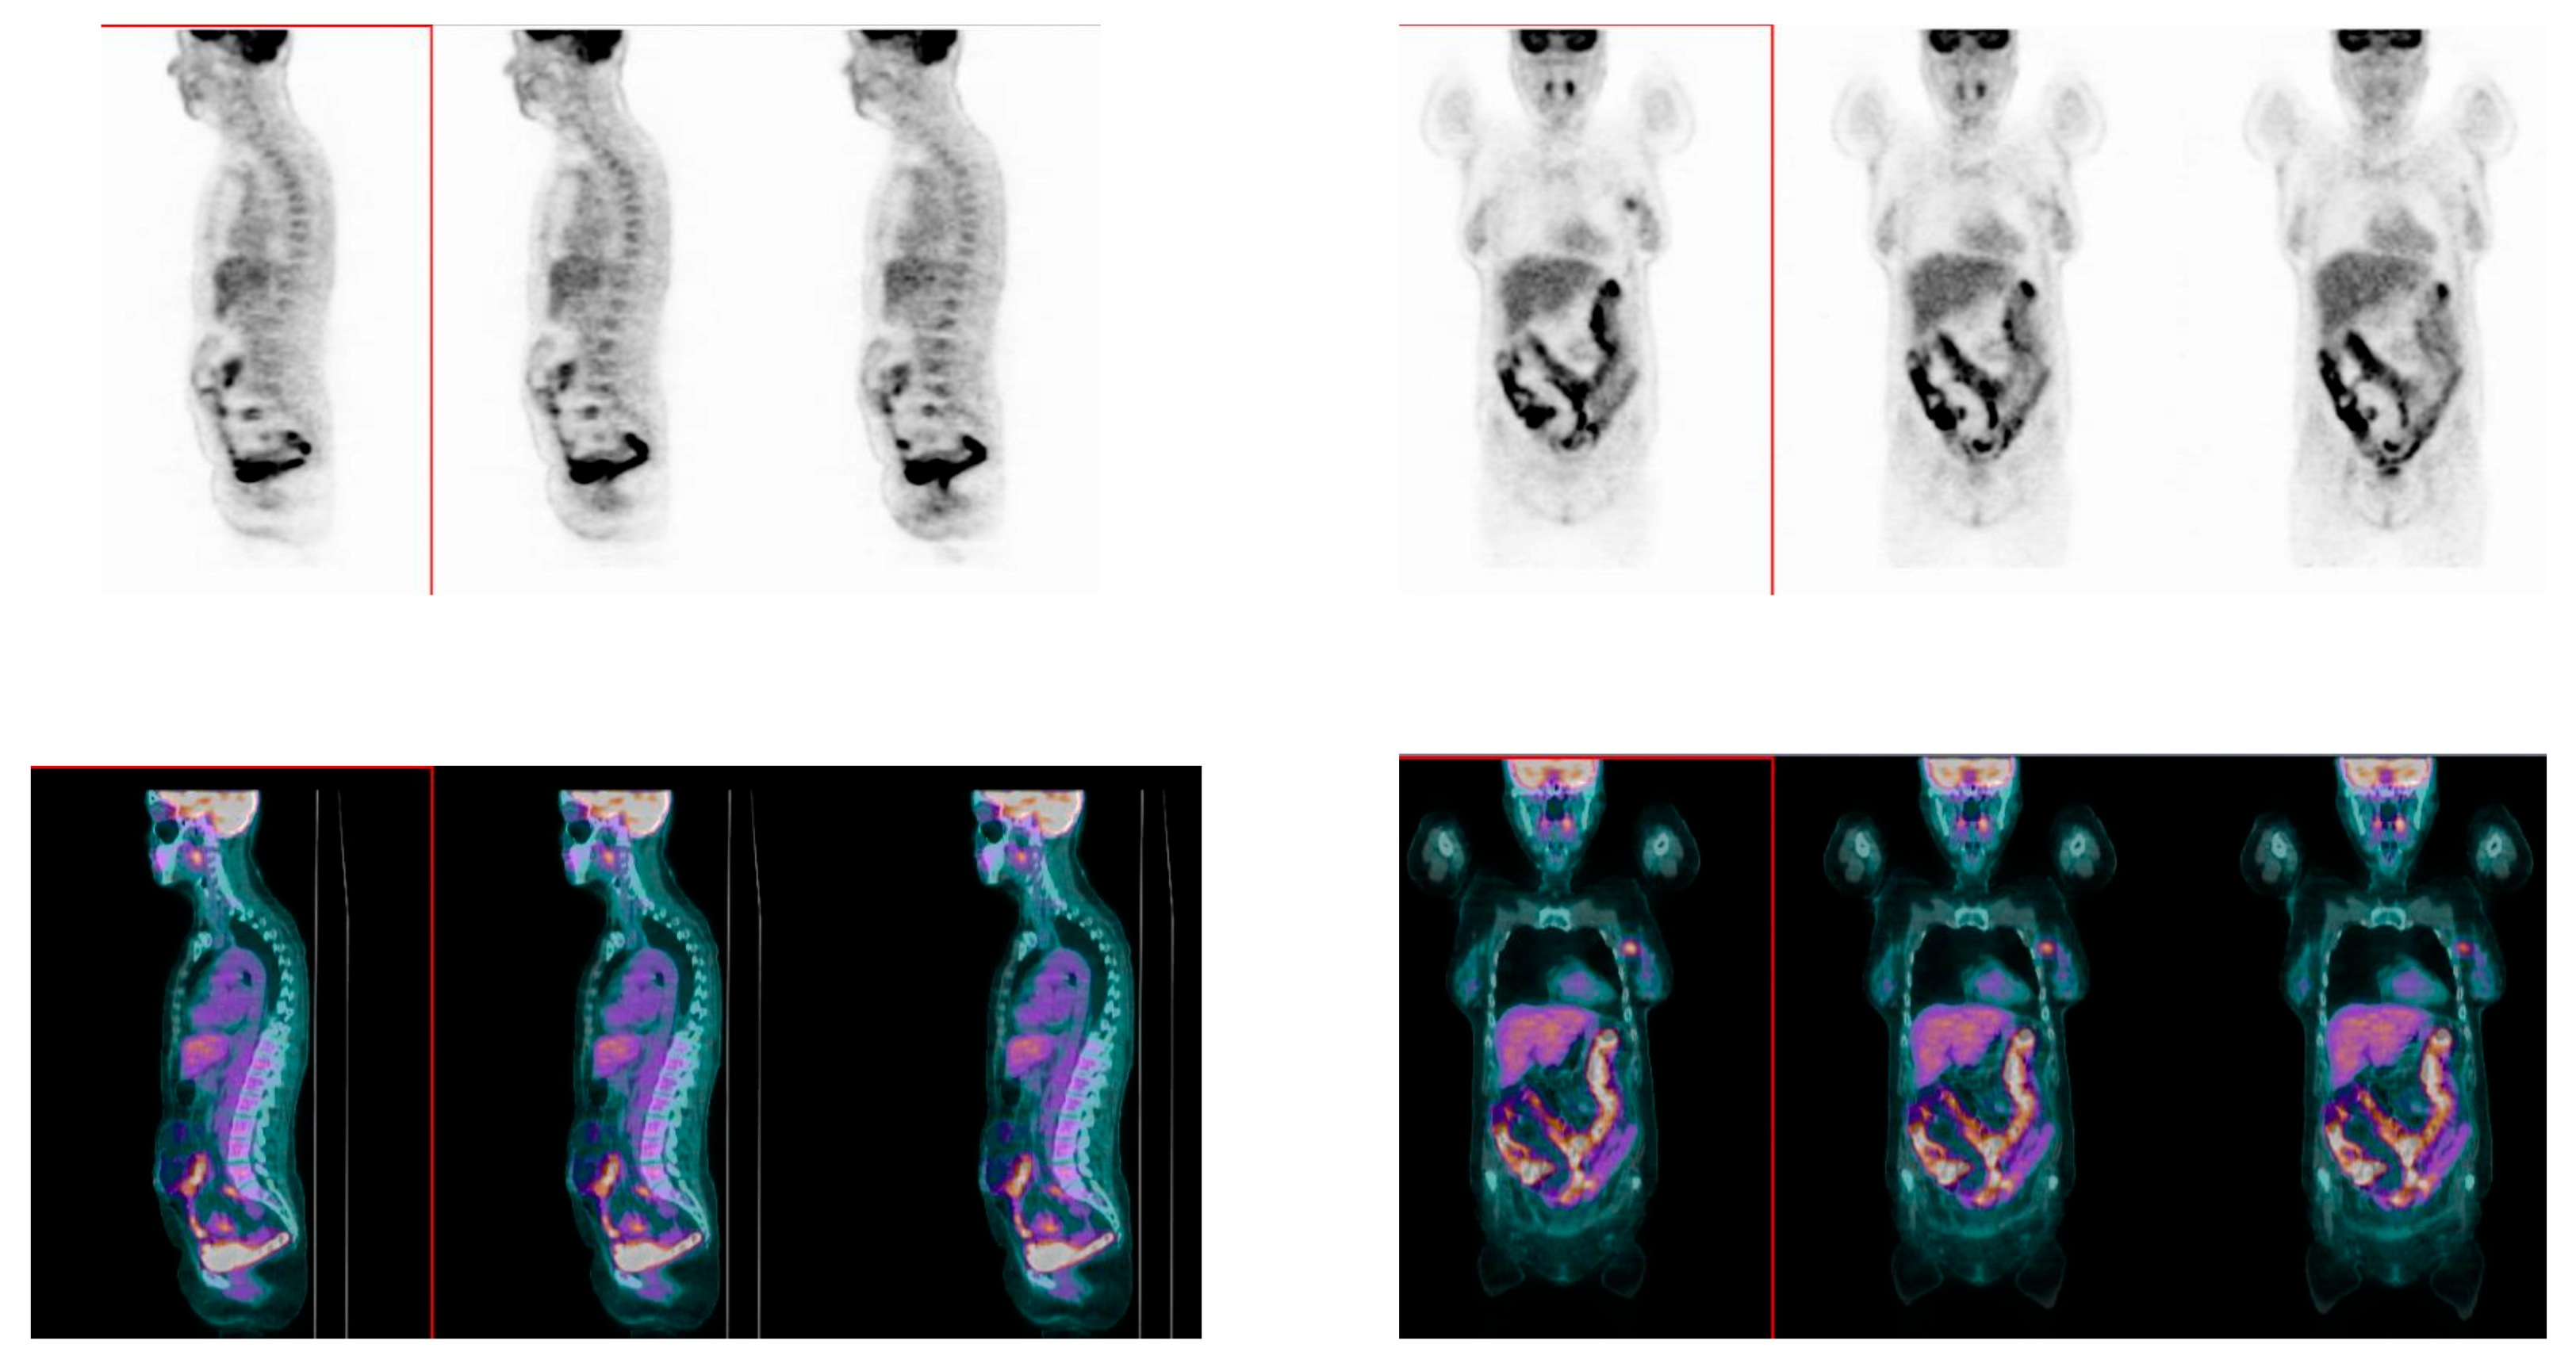

2.3. [18]F-FDG PET/CT Acquisition Protocol